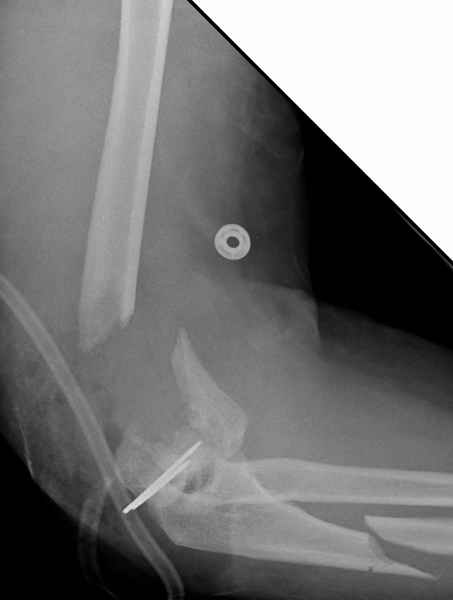

Уважаемые коллеги,Поступила больная 43 лет с 3В открытым переломомправого плеча, мягкотканым и костным дефектом. После получения автотравмы, первичная обработка сделана в другом учреждении, затем переведена к нам.

При первичной обработке сделан дебрайдмент, ревизия раны, суставной фрагмент плеча состоящий из трех частей: головчатая и трохлеа, зафиксировал друг к другу двумя спицами, лучевой нерв не работает, но повреждения не было обнаружена на протяжении 13 см, также обнаружен интактный локтевой нерв на протяжении 3 см. Временный наружный фиксатор наложен на верхнюю конечность, ваккумный постоянный отсос на мягкие ткани. Дважды проба из раны на чувствительность аэробную и анаэробную микрофлору - пока отрицательная.Мой план на сегодня, через пару часов: фиксация локтевой кости 3.5 мм локинг пластиной, возможно для стабилизации маленьких дистальных фрагментов и для удержания в олекранон фосса, провести шуруп или спицу, спицы через олекранон, цемент с антибиотиком на месте дефекта и ждать, когда мои коллеги из пластической хирургии закроют рану.Мои партнеры советуют, после заживления - дистальную артропластику или костный графт, но у меня сомнения, некуда зафиксировать в дистальном отделе, у кого другие мнения?Джолдас Кульджанов